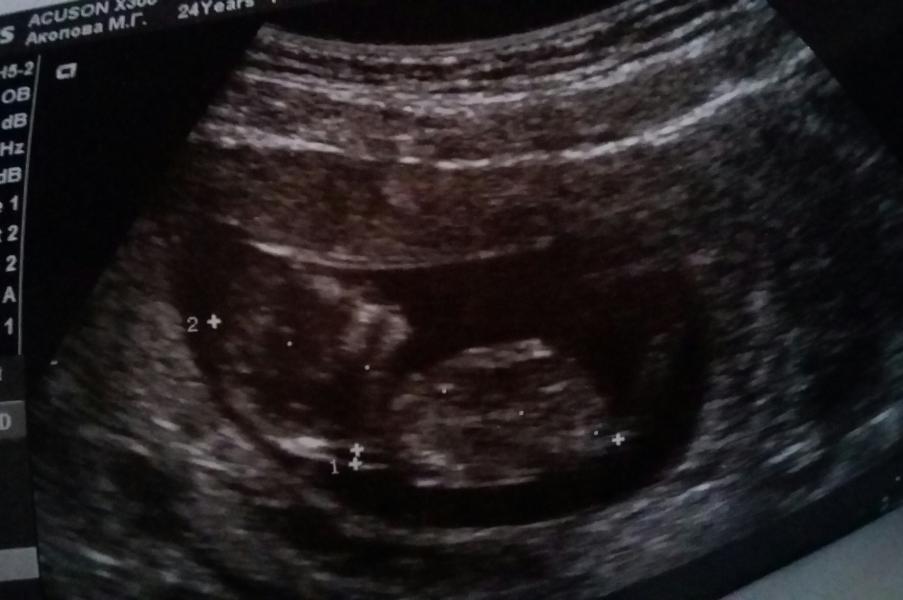

Привет Миииир✌Пошли сегодня на 1-вый скрининг. По совету одной из девочек Мамлайфа пошла В Гемотест на ул Мира "Мытищи" Врач Жилина Ирина Леонидовна.Просто офигенный узист.Зашли с Мужем.Все показала,объяснила,посмеялись над тем, какой танцор малыш😂😂😂Не давал сердечко слушать своими танцами.🙈Все у нас хорошо👍Между ногами не понятно что пока.Пипка торчит,но точно не понятно.Видели бы вы лицо моего мужа довольное.Он пацана свова хочет😂Я все надеюсь на девчушку.А вообще главное не это.Главное здоров...